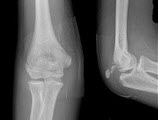

45、单项选择题

男,6岁,右肘部外伤,结合图像,最可能的诊断是()

A.右肱骨远端骨折

B.右肱骨内上髁骨折

C.右肱骨外上髁骨折

D.右尺骨鹰嘴骨骺损伤

E.右尺桡脱位